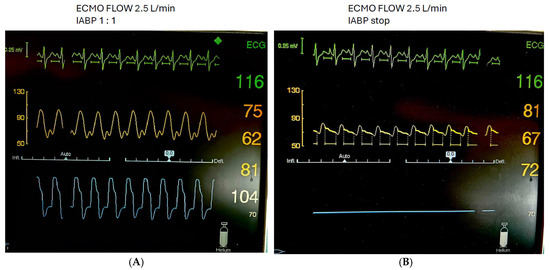

Measurements, performed by a single investigator skilled in echocardiography, were initially obtained on 1:1 IABP augmentation mode. IABP support was then gradually decreased in increments of 10 min to 1:2 and 1:3, followed by a complete IABP stop for 10 min. After reaching a stable hemodynamic condition at the complete stop, the measurements were repeated (Figure 2). VA ECMO flow, sweep gas, mechanical ventilatory support, and vasopressor/inotropic therapy remained constant during the measurements. Only norepinephrine and dobutamine were used in this patient cohort. The degree of vasopressor/inotropic support was expressed as catecholamine index.

Figure 2. Patient with cardiogenic shock on VA ECMO and concomitant IABP with 1:1. Mode (A) and IABP stop (B).